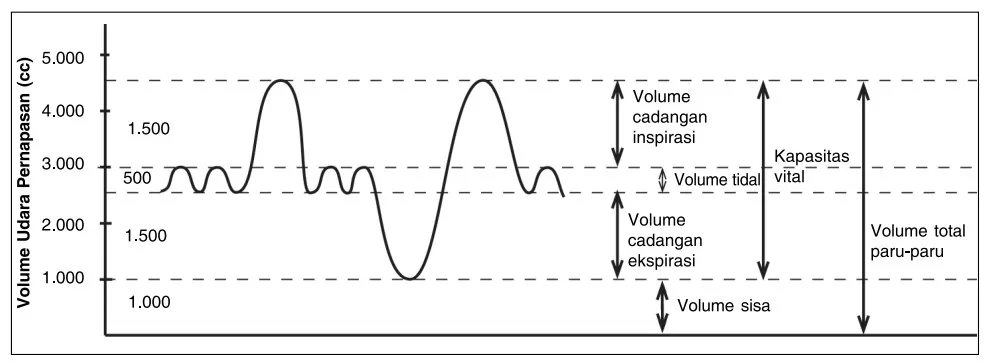

Volume udara pernapasan sangar bervariasi, sebab dipengaruhi oleh cara dan kekuatan seseorang melakukan respirasi. Pada orang dewasa, volume udara berkisar antara 5 – 6 liter. Udara pernapasan manusia dibedakan menjadi beberapa jenis sebagai berikut.

- Udara pernapasan biasa (Volume Tidal). Merupakan udara yang masuk dan keluar paru-paru pada saat pernapasan biasa. Besar volume tidal sebanyak 500 mL.

- Udara cadangan inspirasi (Volume Komplementer). Merupakan udara yang masih dapat dimasukkan ke dalam paru-paru secara maksimal, setelah melakukan inspirasi normal. Besar volume komplementer adalah 2500 – 3000 mL.

- Udara cadangan ekspirasi (Volume Suplementer). Merupakan udara yang masih dapat dikeluarkan dari paru-paru secara maksimal setelah melakukan ekspirasi biasa. Besarnya volume suplementer adalah 1250 – 1300 mL.

- Udara residu. Merupakan udara yang tesisa di dalam paru-paru yang berfunsi untuk menjaga agar paru-paru tetap dalam keadaan mengembang. Besarnya udara residu adalah 1200 mL.